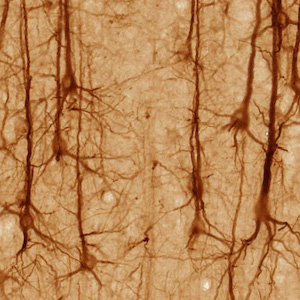

Finally, the authors exposed the rats to the scents and examined what happened in their brains. Regions of the amygdala (associated with fear) and the hypothalamus (associated with emotion) lit up in the addicted rats, demonstrating a link between these brain circuits and the rats' heroin-seeking behavior.